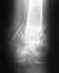

Очень сильно беспокоит укорочение кости левой голени после горнолыжной травмы 3 года назад.

Перелом был закрытый с небольшим смещением,без обломков. 4 месяца стоял аппарат Костюка, затем некоторое время ходила с тростью. Последний год беспокоит сильный дискомфорт, связанный с укорочением кости голени примерно на 1.5-2см, следствие чего - перекос всего тела на левую сторону. Неправильно развивается все части тела, так как мне всего 21. Обращение к специалистам ничего не дало - говорят, что это нормально. Но зная свои ощущения, уверенна, что очень надо вернуть прежнюю длину и исправить перекос тела (и следующую за этим большую нагрузку и дискомфорт в позвоночнике). Помогите, пожалуйста!! что можно сделать??? Желательно бы без хирургического вмешательства! С уважением, Ана.Очень жду ответа: vinila@mail.ru

В первую очередь надо определиться не по ощущениям, а по фактам, есть ли дефицит длины, за счет какого отдела, и какой точно по величине.

Обычно укорочение до 2 см не дает значимых проявлений. А уж "перекос всего тела на левую сторону" или то, что Вы так называете, скорее всего, обусловлен чем-то другим.

Шутки шутками, но для того, чтобы проблему решать, надо ее четко определить. Будет точный диагноз, будет и план лечения, и прогноз. Надо для начала сделать сравнительные рентгенограммы здоровой и поврежденной голени. Амплитуда движений в голеностопном суставе полностью восстановлена, если сравнить со здоровой стороной?